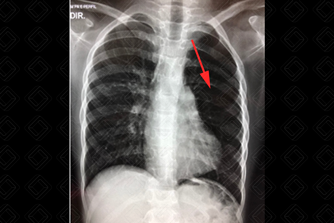

Texto alternativo para a imagem Figura 2. Créditos: Dra. Elazir Mota - Rio de Janeiro/RJ

Descrição da figura 2: Paciente neonato, 2 dias de vida, com hipertransparência e aumento de volume no hemitórax esquerdo (seta vermelha), causando desvio do mediastino contralateralmente. Foi realizada tomografia computadorizada do tórax que confirma enfisema lobar congênito.

• Causas pulmonares: Congênitas: enfisema lobar congênito ou hiperinsuflação pulmonar congênita (figura 2), atresia brônquica (figura 3), malformação pulmonar congênita (MAC); adquiridas: síndrome de Swyer James, causas de obstrução brônquica parcial do brônquio (aspiração de corpo estranho, plug mucoso, tumor endobrônquico), tromboembolismo pulmonar maciço, pneumectomia;